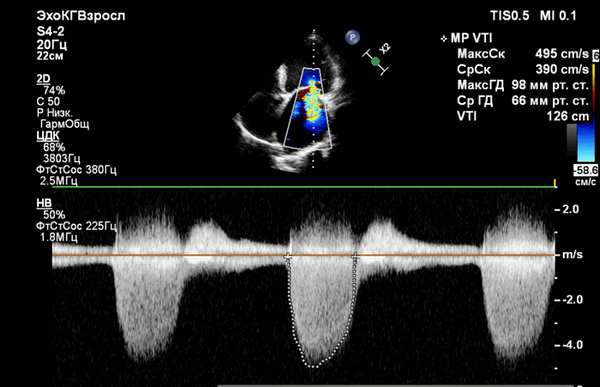

Эхокардиография и цветное допплеровское картирование

![Эхокардиография после протезирования клапанов]()

Допплер-эхокардиография позволяет выявить скорость потока через протез клапана, что позволяет определять градиенты давления с использованием модифицированного уравнения Бернулли (градиент давления = 4 х скорость в квадрате). Отличная корреляция была установлена между допплеровским методом и инвазивным измерением давления двойным катетером, выполненным одновременно на различных протезированных клапанах. Однако, несколько моделей инвитро показали завышение градиента на аортальном протезе, которые определяются по допплеровским скоростям по сравнению с катетер-производными градиентами. Расхождение данных меньше в протезе с большим опорным кольцом. Потенциальные источники в разнице между допплер-производными и катетер-производными перепадами давления на протезах должны быть учтены, но это не является большой проблемой в выявлении дисфункции протеза.

Непрерывно-волновая допплерография может быть использована для оценки функциональной площади отверстия протеза аортального и митрального клапанов. Время полуспада давления (РНТ) метод, используемый для определения стеноза нативного митрального клапана, обычно переоценивает площадь митрального протеза. Протез клапана изначально стенотический в разной степени по сравнению с соответствующим родным клапаном, поэтому скорость потока через нормальный протез клапана выше, чем ожидаемый на родном клапане. Нормальная скорость протезного потока (следовательно, максимальный и средний градиенты давления) зависит от типа и размера протеза, его расположения и сердечного выброса. Следовательно, очень важно знать нормальные диапазоны скоростей потока для определенных типов протезов для сравнения с измеренными значениями. Поскольку гемодинамика протеза зависит от различных факторов, рекомендуется выполнить базовое допплеровское эхокардиографическое исследование в раннем послеоперационном периоде (сделать «отпечаток» функции протеза), так что он может быть использован в качестве эталона для сравнения с последующими исследованиями. Обе ситуации как регургитация, так и обструкция может привести к увеличению скорости потока через протез. Увеличение скорости потока указывает на то, что имеется несоответствующее меньшее отверстие, когда в протезе есть препятствие и при этом нет клинически значимой регургитации или увеличивается объем потока через протез (есть значимая регургитация).